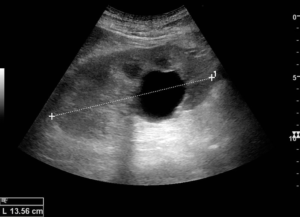

- Ультразвуковое исследование почек, позволяющее определить размеры, расположение и характер содержимого в капсуле новообразования;

- Магнитно – резонансная и компьютерная томографии, использующиеся для составления более полной картины и уточнения результатов, полученных благодаря УЗИ;

На основе результатов обследования и под контролем УЗИ в области локализации капсулы выполняется прокол кожи и мягких тканей. Специальной иглой уролог производит прокол капсульной стенки и извлекает из нее содержимое.